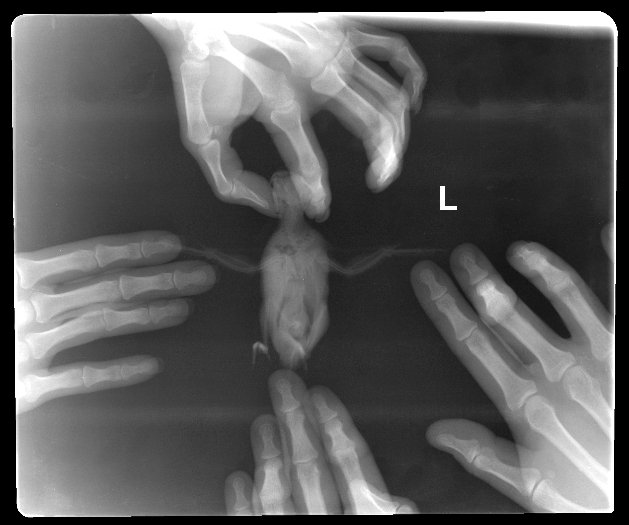

1 Возраст, пол Около 8лет, девочка 2 Как давно у Вас птица? Около 8 лет 3 Как давно болеет? Голос стал меняться в течение недели, фыканье(дыхание затруднительное) , чихание и запор периодически появлялись и раньше 4 Какие симптомы? Чихает , голос перестал быть звонким, затруднительное дыхание "фыкает", иногда будто бы страдает запором и пытается лапкой попку почесать 5 Какой помёт? (фото) 6 Была ли рвота? нет 7 С чего началась болезнь?(смена корма, простудился, ушибся, съел что-либо подозрительное и т.д.)? Ничего такого не было, просто стала замечать странное дыхание у птички, будто носик забит и она "фыкает" затруднительно, чихает и при этом брызгает соплями или ещё чем, но не всегда! Иногда сухой чих. в остальное время никаких выделений не было и нет. И Наверное, с неделю стала замечать, как голос её стал меняться, он перестал быть звонким, будто бы носик забит. И иногда складывается такое ощущени, будто у неё запор и она лапкой попку пытается почесать, но это редко. В остальном поведение такое же - активная, аппетит хороший, любопытная, утром достаточно громко поёт, а к вечеру голос садится. 8 Чем лечили? Не лечила, сделала рентген только, один врач сказал, что не работают передние воздушные мешки, а другой врач нашла опухоль над сердцем и сказала, что не лечится?? 9 Меняли корм, открыли новую пачку? нет 10 Есть растения, мог погрызть? нет 11 Что мог сгрызть?/обои, любой предмет?/ ничего такого не грызет 12 Пользуетесь дезодорантами, химикатами? Фумигатор? Есть ли любые запахи?/Ремонт?/ нет 13 Где живёт птица, кухня, комната? /Курение, посуда с тефлоном, пища не пригорала?/ в спальне, запахов нет 14 Название корма? РИО основной рацион 15 Что даёте кроме корма? сенгальское просо, овощи, фрукты, каши на воде, иногда пророщенную зелень, песок для птиц vita, омега, мел 16 Что ест с Вашего стола? ничего 17 Какие витамины, название? не давала 18 Какие мин подкормки, названия? Грызёт, клюёт? Песок вита, мел. И грызёт и клюет 19 Какую воду даёте и как часто меняете воду в поилке?/Водопроводная, фильтрованная, кипяченая, если покупная, какая?/ фильтрованная 20 Какая упитанность? Худой или полный? Крепенькая 21 Не появлялись ли в доме новые птицы в последние два месяца? Если да, то подробнее об этом. нет 22 Содержится ли птица одна? Если есть другая птица (птицы), каково ее (их) здоровье? одна 23 В доме есть грызуны? нет 24 Страна,город Россия, пенза -